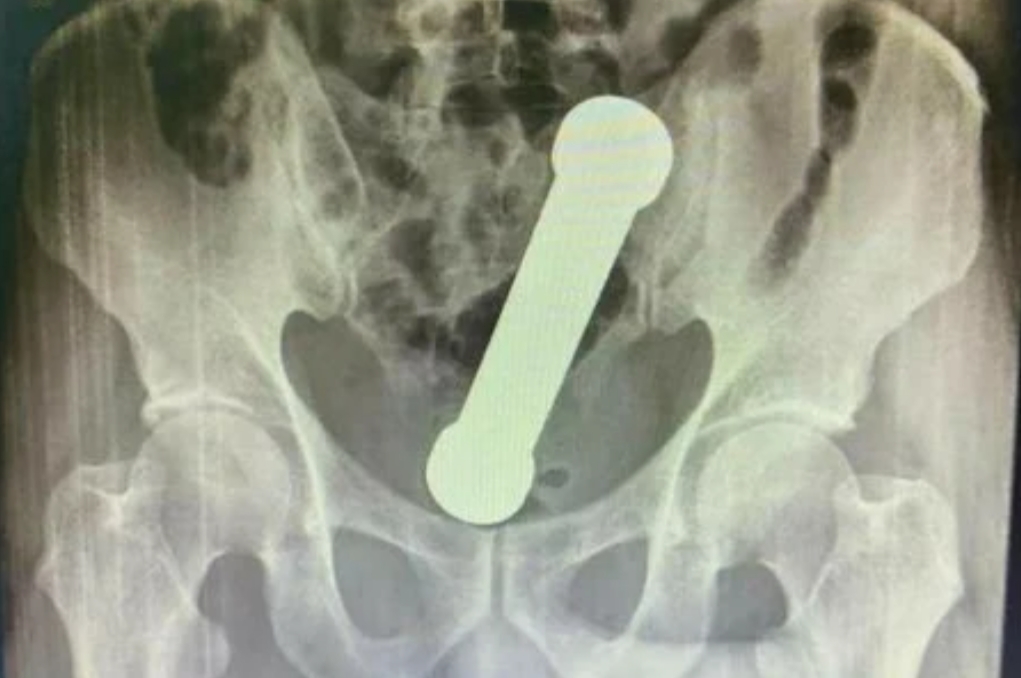

Ao realizarem um exame de raio-X, os médicos encontraram um peso de dois quilos, de cerca de 20 centímetros de comprimento, como os que são usados em academias de ginástica para exercícios de braço, dentro do homem.

O haltere estava entre o reto e o intestino grosso do paciente, que, depois do exame, admitiu ter introduzido o peso de academia no corpo para obter satisfação sexual.